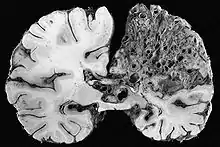

- angiome caverneux (ou « cavernome cérébral ») ; malformation vasculaire située en grande partie dans le cerveau, généralement non détectée, sauf lorsqu'elle cause des crises convulsives ou des hémorragies cérébrales (fréquence : 1 sujet sur 1 000, avec forme familiale dans 20 % des cas). Trois gènes situés sur les chromosomes 7 et 3 semblent impliqués ;